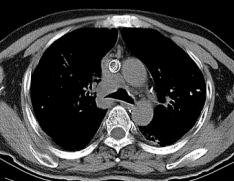

经过12次放疗,患者气短明显改善,从全程依赖无创呼吸机逐步过渡到间断使用;完成17次放疗后,患者仅需高流量鼻导管吸氧,胸闷气短大幅缓解,影像学显示肿瘤病灶显著缩小。令人欣喜的是,患者从完全无法平卧,现已基本能平躺休息,生活质量得到极大提升。

放疗后